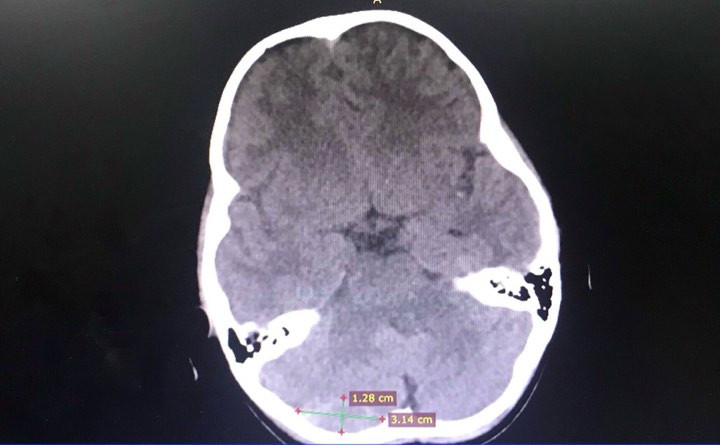

Bé gái suýt chết vì chấn thương sọ não do cha mẹ chủ quan ảnh 1Hình ảnh máu tụ ngoài màng cứng não của bệnh nhi.

Đến 4 giờ sáng hôm sau, bé gái kêu đau đầu và bắt đầu ói mửa. Ngay sau đó, gia đình đã đưa em đi cấp cứu tại khoa Cấp Cứu – Bệnh viện quận Thủ Đức. Sau khi nhập viện kiểm tra và theo dõi, bé T được phát hiện bị máu tụ ngoài màng cứng hố sau bên phải. Ngay lúc này, bé được chỉ định can thiệp lấy máu tụ để giải ép do các bác sĩ khoa Ngoại Thần Kinh phối hợp với các bác sĩ hồi sức Nhi, bác sĩ gây mê tiến hành.

Sau phẫu thuật một ngày bé T đã được chỉ định chụp CT lại để kiểm tra, đánh giá. Bé tỉnh, da hồng hào, vết mổ khô. Bé nằm tại khoa Ngoại Thần Kinh khoảng mười ngày sau khi mổ để được theo dõi. Hiện tại, bé T đã được cắt chỉ và xuất viện về nhà.